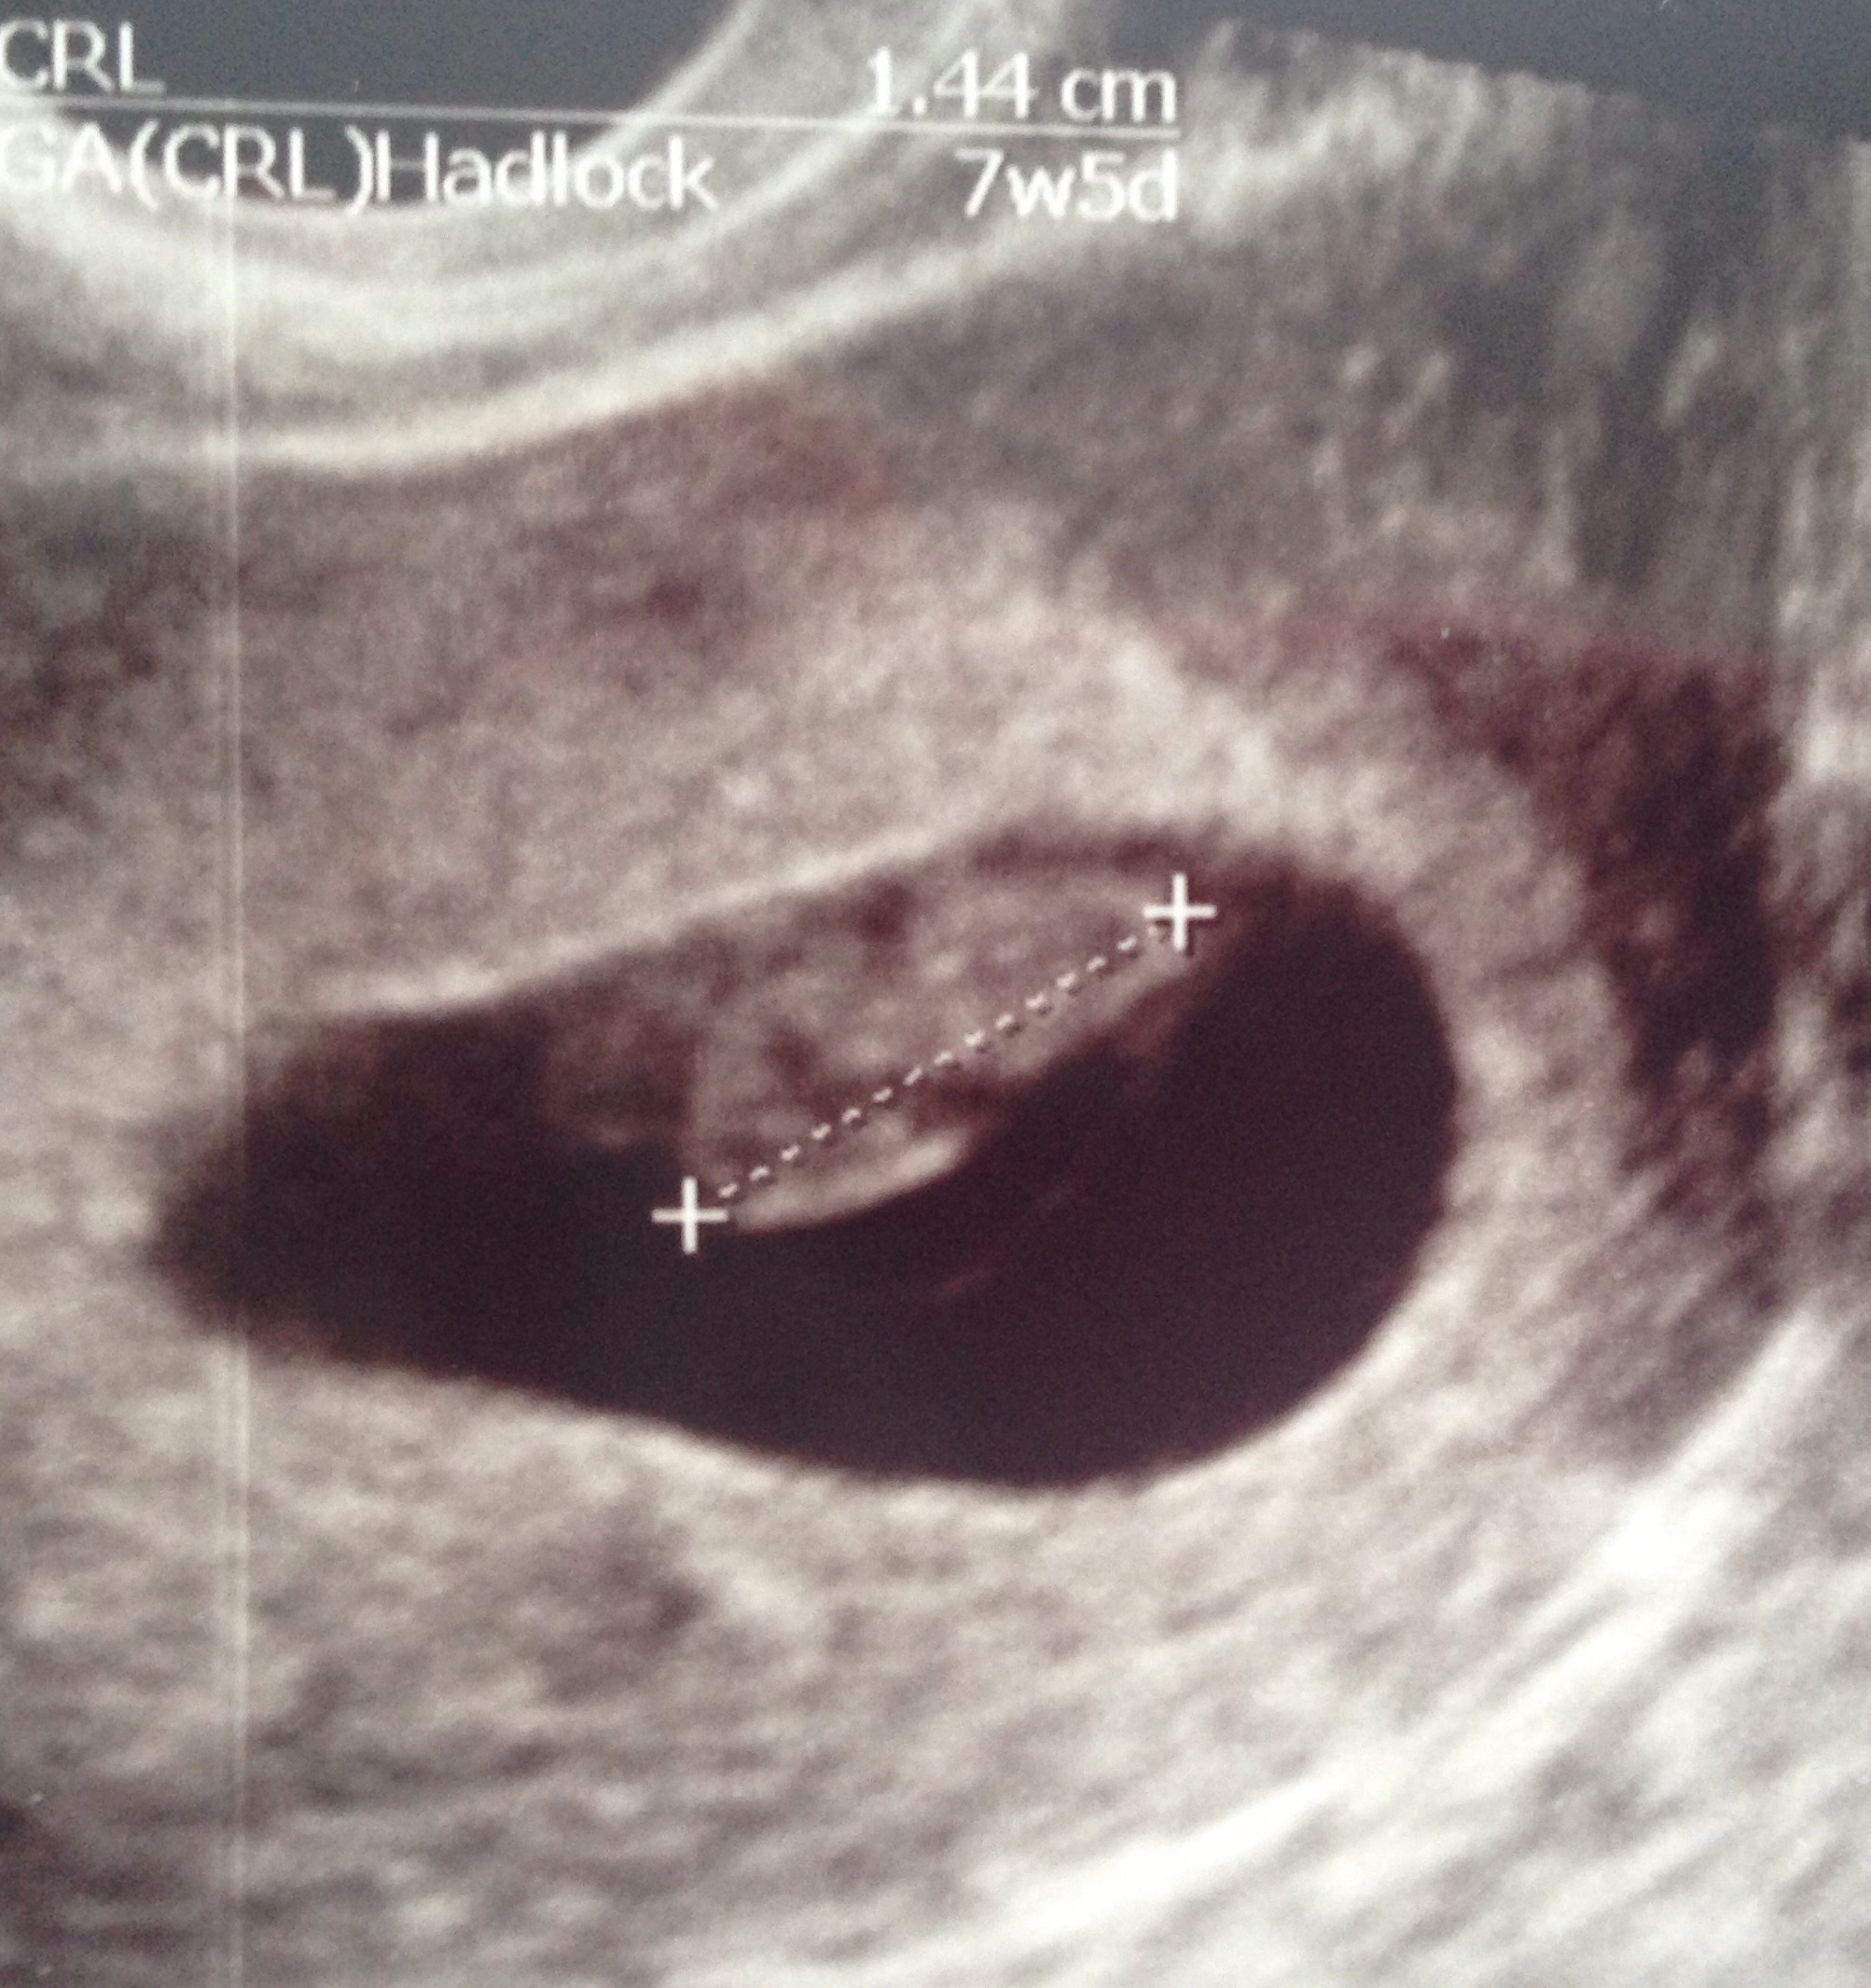

Here is our little Bean! The ultrasound tech thinks the due date is around 4/13/16 (originally thought it was 4/6/16). That puts me at about 7 weeks, 5 days now. Heart rate was 141 and baby measures about 1.5 cm long. We also got to see and hear the heart beat, which is the coolest thing ever!